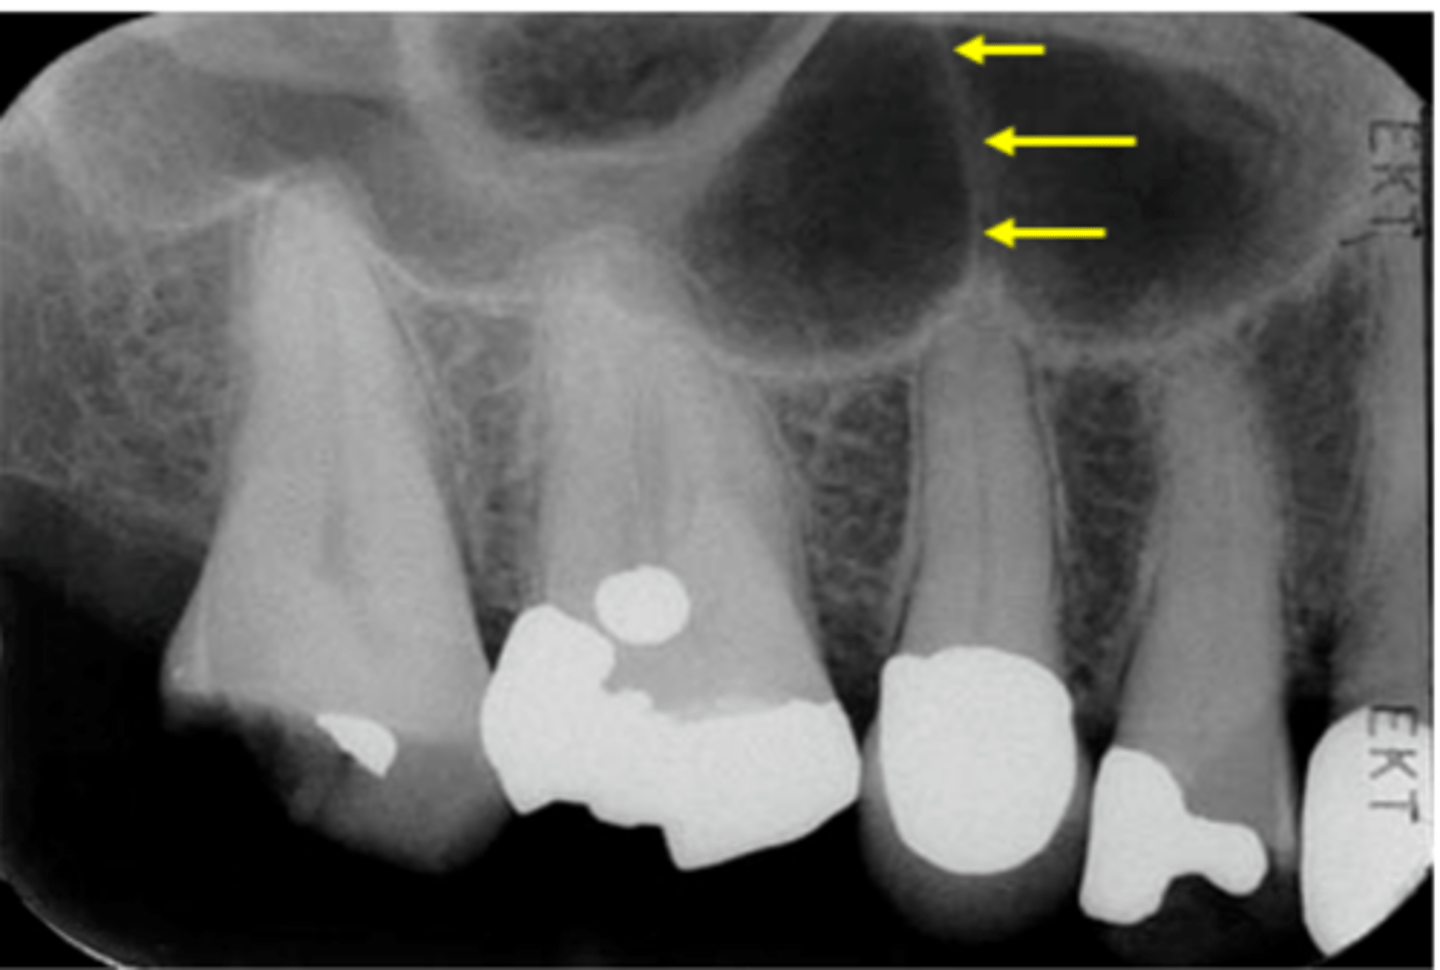

New cards

Zygomatic process of the maxilla

Identify the structure

19

yellow line- zygomatic process

white arrow - zygomatic bone

Identify the two structures

42

Hamulus

Name the elongated radiopacity indicated by #5.

43

Lateral pterygoid plate

Name the large radiopacity with a rounded inferior margin indicated by #4.

Zygoma

Name the horizontal radiopaque line labeled #2.

Floor of maxillary sinus

Name the curved line scalloping between tooth roots labeled #3.

46

Coronoid process

Name the curved, conical structure outlined in the bottom left corner of the image.